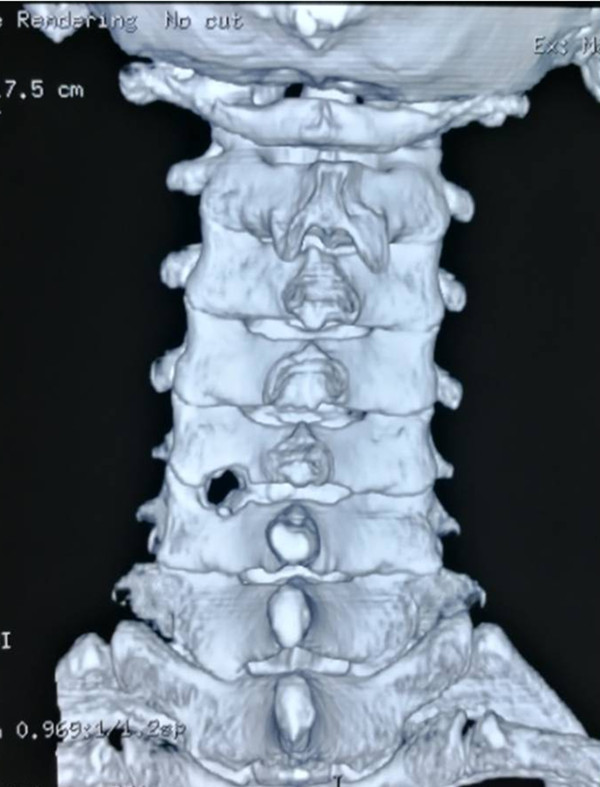

术后三维CT